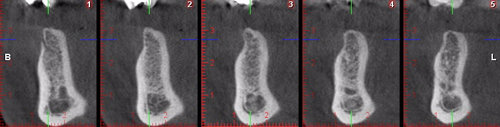

Palabras Clave: ELG: Estereolitográfico OH: Oclusión Habitual ORC: Oclusión en Relación Céntrica Paciente de 35 años de edad ,sexo masculino que lo derivan para implantar el tercer cuadrante. A la auscultación presenta ruidos articulares de tipo chasquido que remiten temporalmente luego de limitación de apertura bucal y maniobras quinesiológicas distractoras. También se observan recidivas de caries en algunos empastes y falta de disclusión canina de ambos lados. Se estudia el caso desde un punto de vista clínico, scanografico mediante Dentascan y tridimensional mediante montaje en articulador. A partir del scanner se obtienen datos para confeccionar modelo estereolitográfico (ELG),operar en el y construir férula quirúrgica dento-muco soportada. Habitualmente se procede directamente a implantar, dado que ese era el requerimiento del profesional derivante y el deseo del enfermo. Sin embargo, esa actitud enmascararía otro tipo de problemas que la boca presenta. Se consulta al odontólogo derivante, y coincide con mi opinión acerca de que si solo se lo implanta, sin corregir la posición mandibular, la situación de las ATMs, los empastes sin anatomía y la falta de disclusiones, el resultado final no será el deseado y su eficacia masticatoria no funcionará optimamente. Consultado el paciente coincide y acepta ese concepto y entonces procedemos a confeccionar un Jig de Lucia a partir del montaje de estudio, y lo dejamos puesto en boca toda la noche anterior a la consulta, para proceder a realizar un ajuste oclusal al día siguiente sin engramas anteriores, lo que facilita no tener que relajar nuevamente con laminillas de Long. En esta etapa pierde el implante correspondiente a la pieza 4.7 que traía en boca. Estabilizado el sistema, procedemos a la parte quirúrgica, comenzando por instalar la férula, retirar opérculos gingivales mediante bisturí circular, fresado óseo e instalación de implantes ,toma de impresión a cubeta fenestrada (pegando con metacrilato sin cambios dimensionales, los transfers a la cubeta especialmente diseñada.(1º método de pasividad protética utilizado), e instalación de tornillos de cicatrización. Inmediatamente de retirada la cubeta de boca y colocadas las réplicas de los implantes, procedemos a ferulizar los “ápices” de las réplicas para que no sufran movimientos durante el llenado de la impresión.(2º método de pasividad protética utilizado). Controlamos radiograficamente Tres meses después, procedemos a tomar nuevos registros de arco facial, registros intermaxilares en Oclusión en Relación céntrica, montaje de los modelos obtenidos intra operatoriamente y confección de un conjunto de cuatro coronas provisionales de metacrilato en el sector implantado y las correspondientes al maxilar superior. Verificada la perfecta función de todos los componentes, ausencia de todo tipo de síntoma y comprobada la paz en todo el sistema, procedemos tiempo después a confeccionar las fundas definitivas, que constituyen el “cerrojo” de la dinámica del mismo. Por último, corroboramos la oclusión fundamentalmente en lo que hace a la: